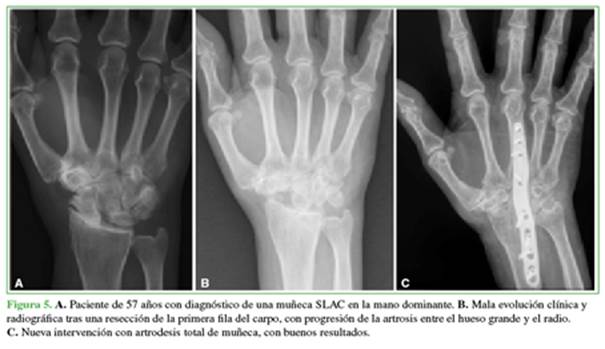

Se estudió la necesidad de otra intervención con una artrodesis total de muñeca por mala evolución clínica. El 12,12% (4 casos) requirió una nueva operación, eran pacientes con SNAC/SLAC II y una lesión condral en el hueso grande detectada durante la cirugía (Figura 5). El tiempo medio hasta la artrodesis fue de 16.5 meses (rango 10-22).

El 12,12% de nuestra muestra necesitó otra intervención, una artrodesis total de muñeca por mala evolución clínica, dato que se corresponde con los publicados en otros estudios, donde se describe una tasa de reconversión a artrodesis radiocarpiana de entre el 4,9% y el 15%.3,7,16 Se corresponden con lesiones diagnosticadas como SNAC/ SLAC II, en las que se detectó una lesión condral en el hueso grande, durante la cirugía, lo cual nos hace pensar que el uso de esta técnica en pacientes con mayor grado de degeneración articular antes de la cirugía puede llevar a un peor resultado operatorio. Consideramos que el extenso tiempo desde el diagnóstico y la inclusión de los pacientes en la lista de espera quirúrgica hasta el día de la cirugía (media 2 años) ha podido influir en los hallazgos intraoperatorios de lesión condral en el hueso grande.